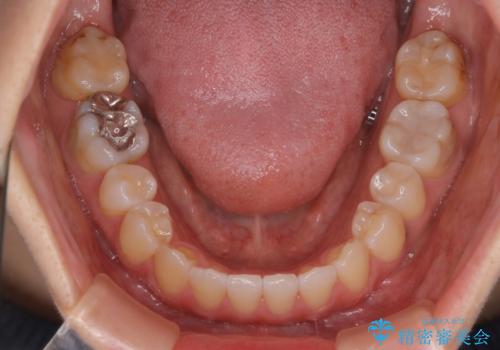

- 受け口で、前歯の嚙み合わせが気になるとの事でご相談にいらした方です。先天的に右上犬歯がなく、左上犬歯も小さい状態でした。矯正治療にて周囲の歯を動かして歯のスペースを確保した上で、被せものにて歯を作っていきました。

歯科技工士さんの熟練した技術により、周囲の歯としっかりなじむ天然歯のような被せ物をお作りすることが出来ました。

矯正治療と補綴治療をうまく組み合わせることで、美しい口元に仕上げることが出来ました。矯正治療、補綴治療をまとめて行える総合歯科治療を体現した治療といえます。